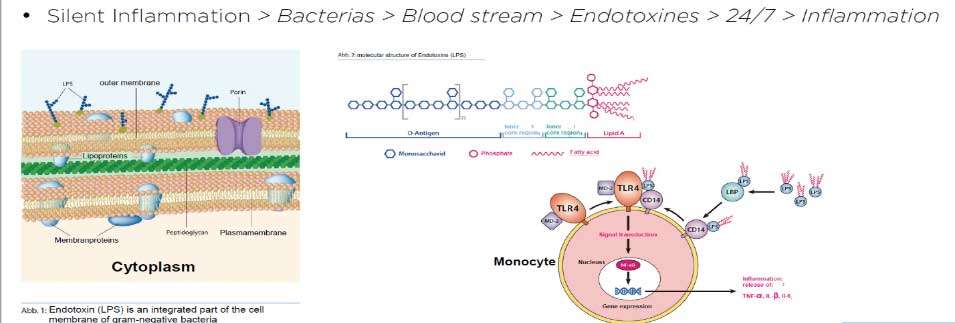

The problem with root canal therapy is it is a flawed therapy, the intention behind doing it is to be able to fully sterilize a tooth which no longer revives blood supply, nerve supply, lymph drainage or any signs of so called life. Anything that is non-vital is usually energetically a break in the circuit. This is the reason why people who have multiple root canal treated teeth complain of chronic fatigue, insomnia as some of the presenting symptom. Any non-vital part of the body is the breeding ground for gram negative anaerobic bacteria and the toxins from this low grade chronic inflammation(silent inflammation) activates the immune system. People with multiple root canal treated teeth usually present with some form of autoimmune condition on their health history.

The problem with root canal therapy is it is a flawed therapy, the intention behind doing it is to be able to fully sterilize a tooth which no longer revives blood supply, nerve supply, lymph drainage or any signs of so called life. Anything that is non-vital is usually energetically a break in the circuit. This is the reason why people who have multiple root canal treated teeth complain of chronic fatigue, insomnia as some of the presenting symptom. Any non-vital part of the body is the breeding ground for gram negative anaerobic bacteria and the toxins from this low grade chronic inflammation(silent inflammation) activates the immune system. People with multiple root canal treated teeth usually present with some form of autoimmune condition on their health history.

Silent inflammation due to root canal therapy, cavitation (avascular osteonecrosis) and titanium implants leads to immune system activation. The intraoral interference fields created by metals, NICOs, bacteria in root canal treated teeth produce highly toxic hydrogen sulfides (Thioether/Mercaptan), metals show cytotoxic, immunological and carcinogenic effects and NICOs (Neuralgia inducing osteonecrosis) consist of increased inflammatory mediators like RANTES, FGF-2 and IL-1ra.